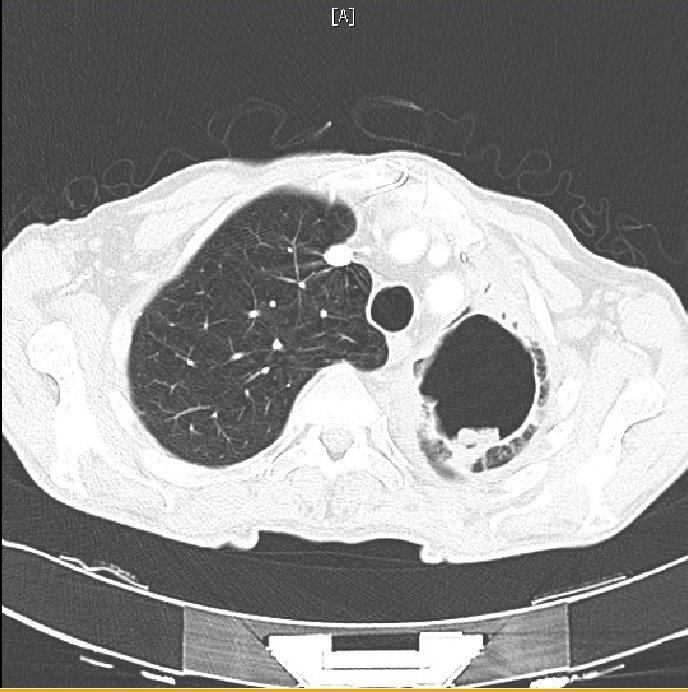

Figure 4. Air-fluid level in apical cavity with adjacent upper-lobe consolidation.

Figure 5. CT Angiography. No pulmonary embolus was identified, a consolidation surrounding the cavity was seen and new “tree-in-bud” opacification was present in the right-lower lobe.

The consolidation surrounding the cavity on CT and the new tree-in-bud opacification are suggestive of pulmonary infection, be it bacterial or fungal. This upper-lobe consolidation is also apparent on the plain chest radiograph, as is an air-fluid level. The above findings would be consistent with bacterial pneumonia, and the presence of an aspergilloma-containing cavity increases the susceptibility to bacterial infection. The clinical picture would also be consistent with a bacterial superinfection – cough productive of green sputum, upper-lobe crackles on auscultation and raised white cell count with associated neutrophilia. Diagnosis would be based on a positive bacterial culture on sputum or bronchoalveolar lavage specimens, and clinical and radiological improvement with appropriate antibiotic treatment.